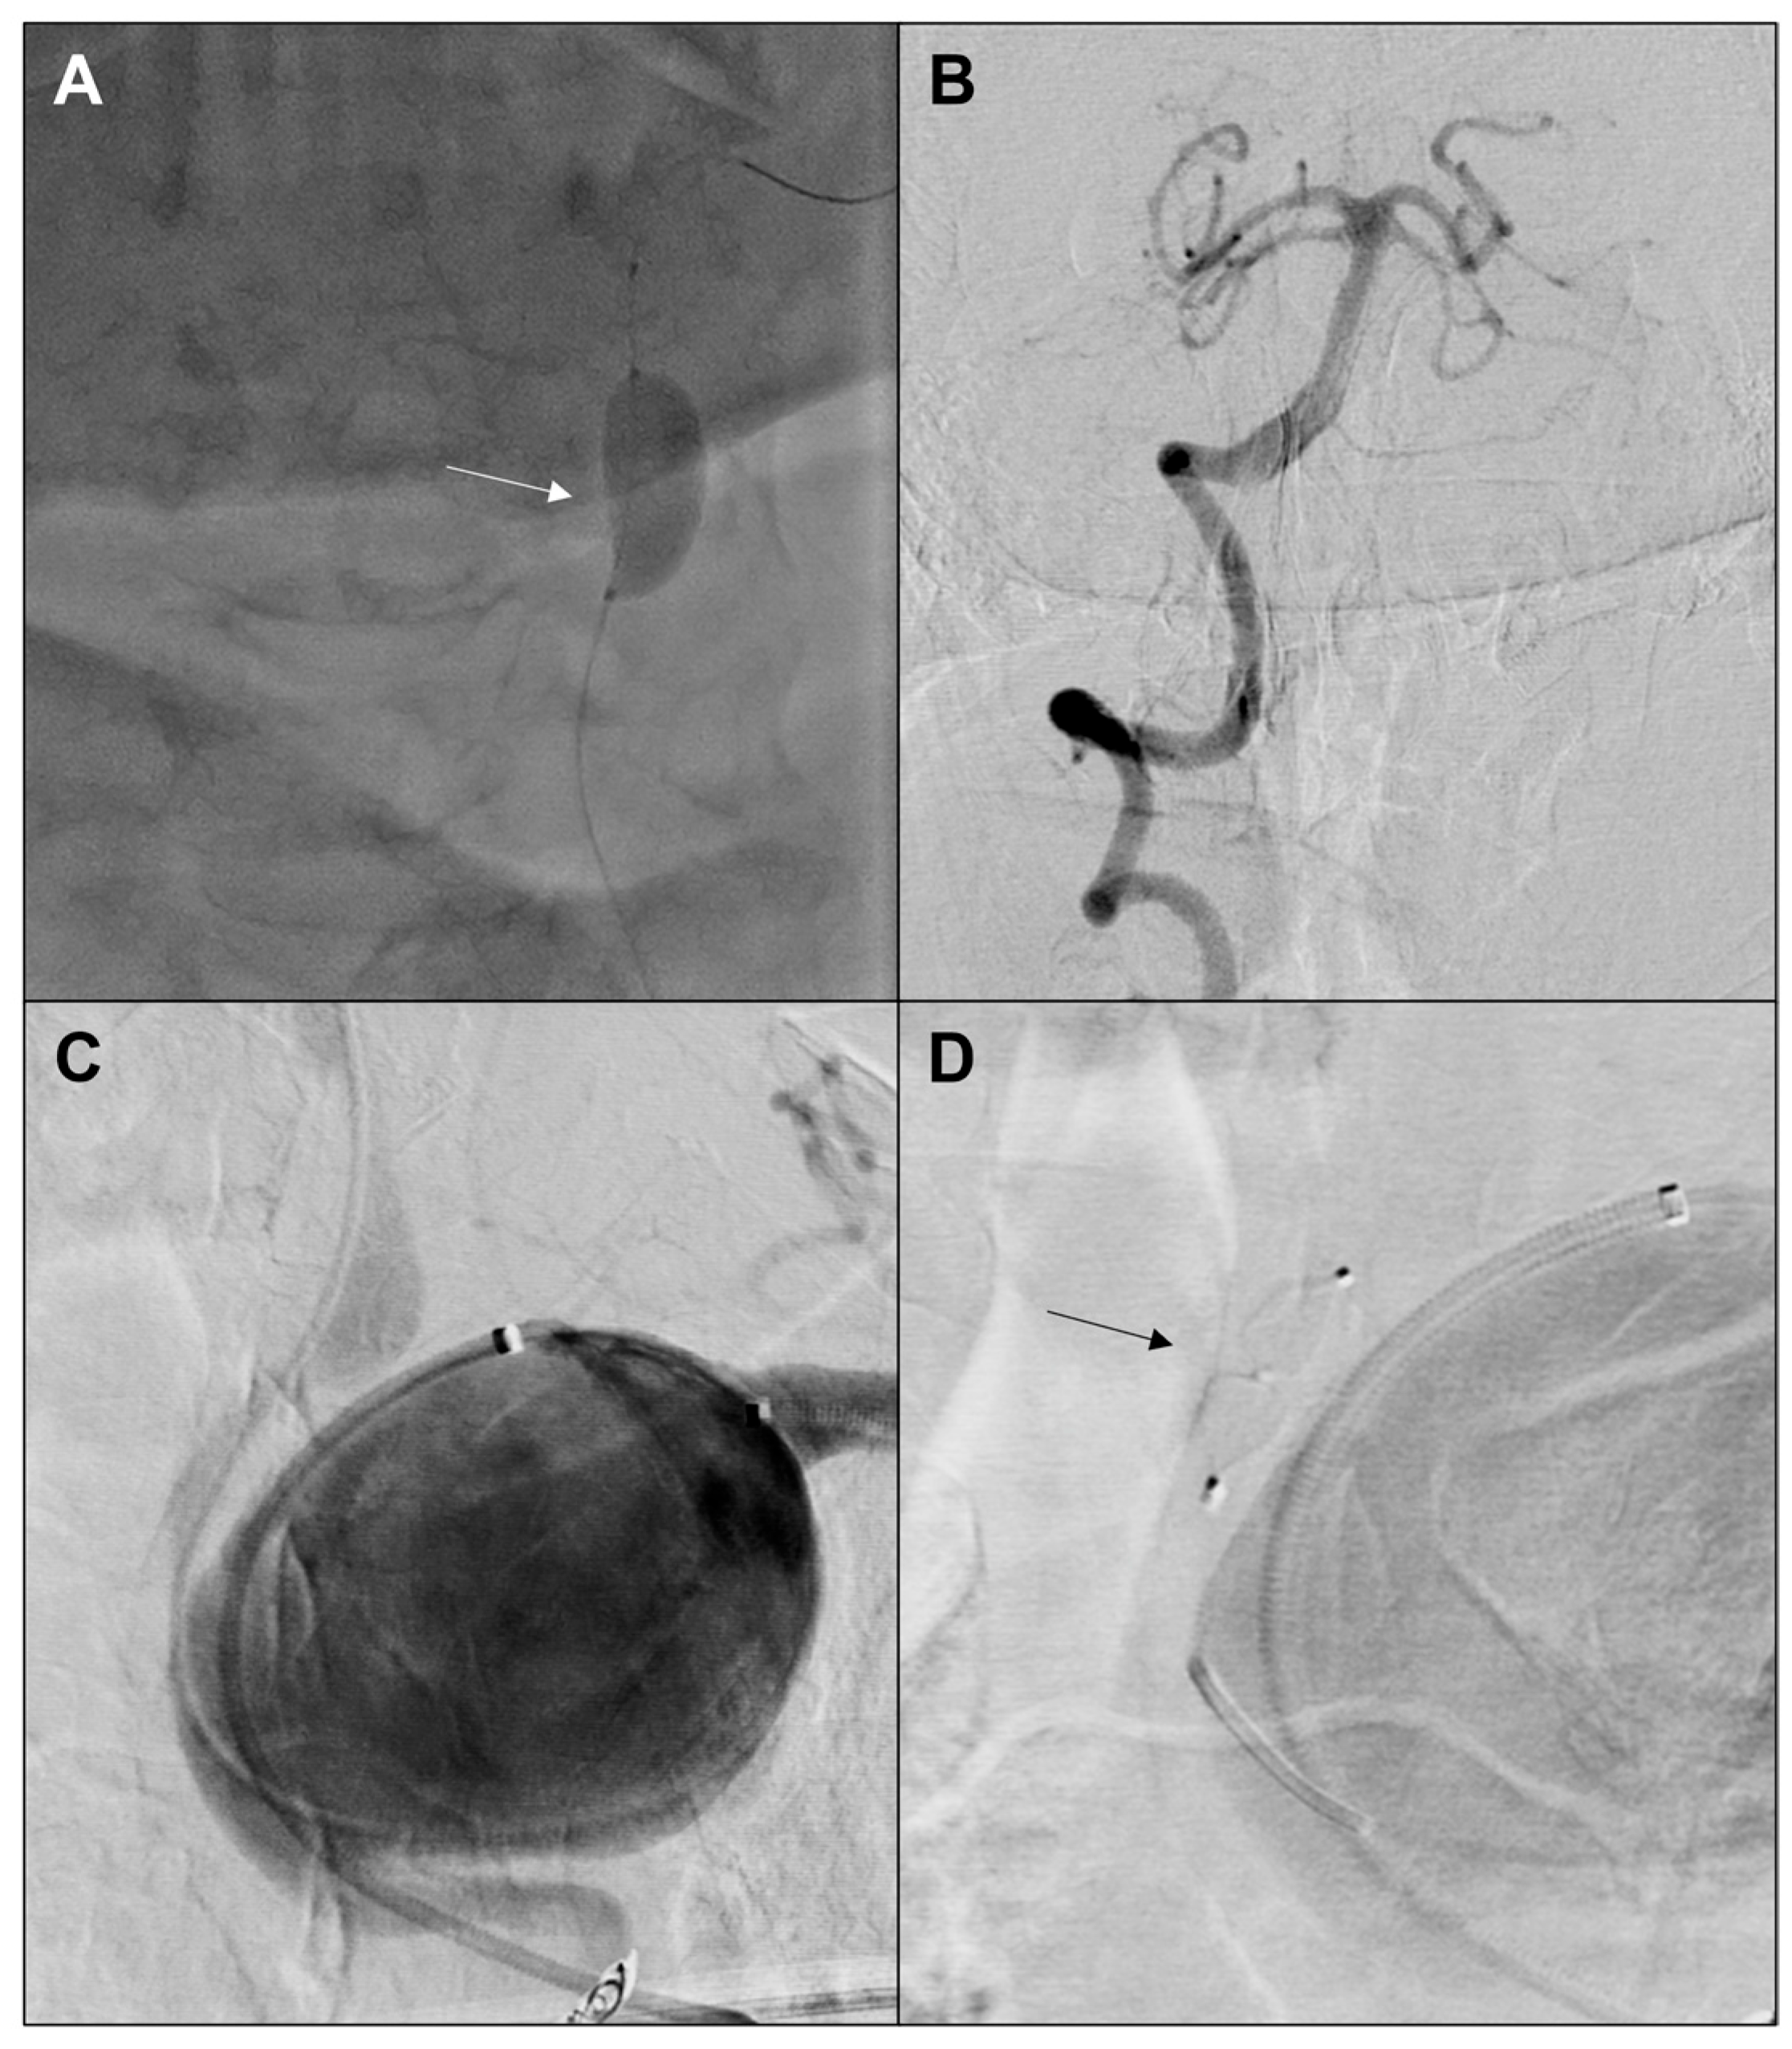

2. Case Report